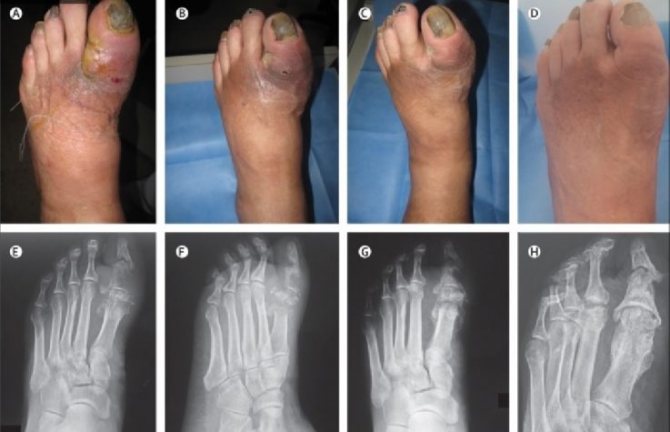

Осложнения флегмоны ноги фото

Операция проводится под эпидуральной анестезией. Такой вид обезболивания позволяет не только хорошо обеспечить анестезию, но и проводить в последующем перевязки и этапные некрэктоми.

Во время операции обязательно проводится мониторинг артериального давления и ЭКГ. Нередко для внутривенных инфузий мы устанавливаем центральный подключичный венозный катетер.

После обработки операционного поля хирург проводит разрез в месте наибольшей флюктуации (зыбления), где обычно наблюдается максимальное скопление гноя. После вскрытия и опрожнения гнойной полости она промывается антисептическими растворами. До этого обязательно берется посев гноя на микрофлору.

После очищения осматриваются окружающие ткани. Все участки с сомнительной жизнеспособностью должны обязательно удаляться, если имеются вскрытые межкостные суставы, то такие пальцы необходимо удалять.

При распространении инфекции вдоль сухожилия необходимо провести дополнительный разрез выше по сухожилию, вне его гнойного поражения. После этого сухожилие пересекается и его пораженный конец извлекается через рану на стопе.

Во время операции по вскрытию флегмоны хирурги руководствуются принципом — не оставлять ничего сомнительного. Рана на стопе заживет, если инфекция будет остановлена, а кровоток восстановлен.

После операции процесс лечения только начинается. Пациенту проводится активная антибактериальная терапия с учетом высеянной микробной флоры, проводятся мероприятия по восстановлению кровотока (ангиопластика и стентирование).

Процесс окончательного выздоровления достаточно долгий. Нередко пациент выписывается на амбулаторное лечение, а потом госпитализируется вновь, для выполнения реконструктивно-пластических операций.